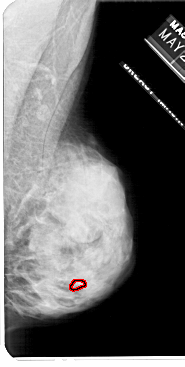

FILE: A_1113_1.RIGHT_CC.OVERLAY

TOTAL_ABNORMALITIES 1

ABNORMALITY 1

LESION_TYPE CALCIFICATION TYPE PLEOMORPHIC DISTRIBUTION CLUSTERED

ASSESSMENT 4

SUBTLETY 3

PATHOLOGY MALIGNANT

TOTAL_OUTLINES 1

BOUNDARY